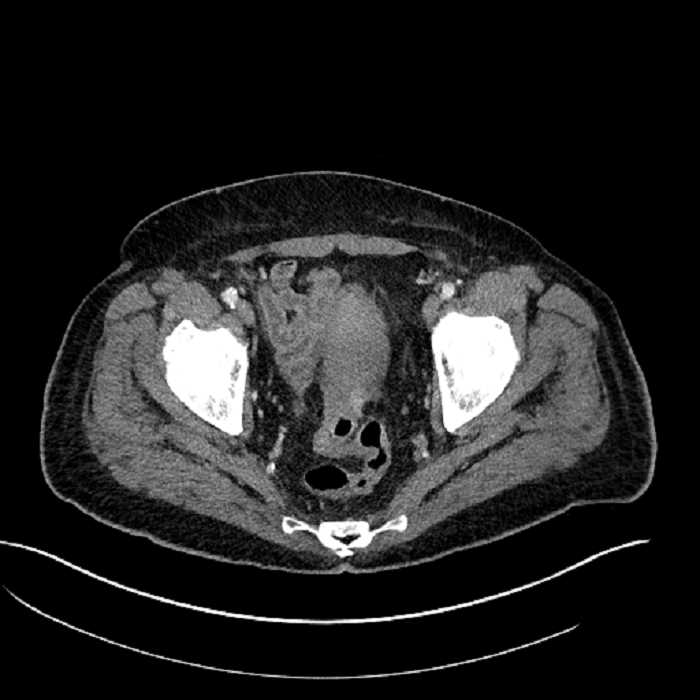

• Mild mural thickening of a segment of the sigmoid colon with adjacent fat stranding and a 1.5 cm fluid and gas collection along the tip of an inflamed diverticulum

• Loss of the normal fat plane between this collection and adjacent loops of small bowel, which demonstrate mural thickening

• No bowel obstruction

• High grade stenosis of the left common iliac artery, with the left internal and external iliac arteries remaining patent

• Ankylosis of both sacroiliac joints

Acute sigmoid diverticulitis complicated by a small contained perforation and a large abscess in the right hepatic lobe. Additional small subcapsular abscesses along the anterior margin of the left hepatic lobe.

Additionally, loss of the normal fat plane between the peridiverticular collection and adjacent thickened loops of small bowel raises the potential for an enterocolonic fistula.

High grade stenosis of the left common iliac artery. The left external and internal iliac arteries are patent.

Hepatic abscess showing the double target sign with low density internally surrounded by a thin inner enhancing rim (red arrow) and ill-defined outer low density rim (yellow arrow). Blue arrow indicates an internal septation. Red arrows: additional smaller subcapsular abscesses. Red arrow: focal contained perforation associated with diverticulitis.